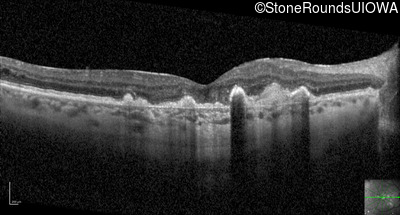

Visit at age: 60 years (Visit 2)

Optical Coherence Tomography - Right - 20/100

Exemplar / OCT Stack

OCT Stack

Infrared Fundus Photograph - Right - 20/100

Exemplar